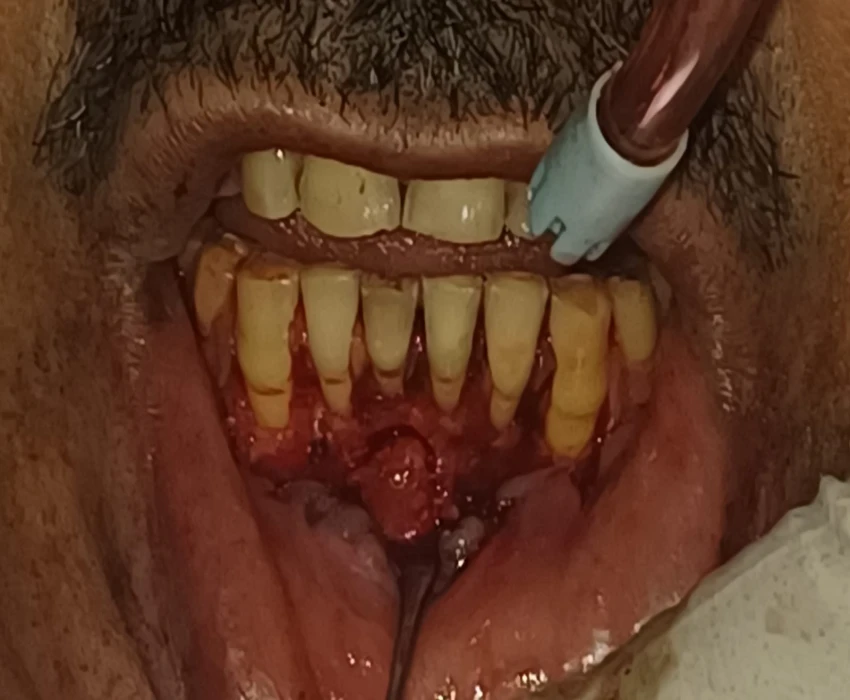

Treatment- non-surgical endodontic treatment was initiated and following obturation of the canal a periapical surgery including curettage, apicectomy, and retrograde filling with MTA was performed.